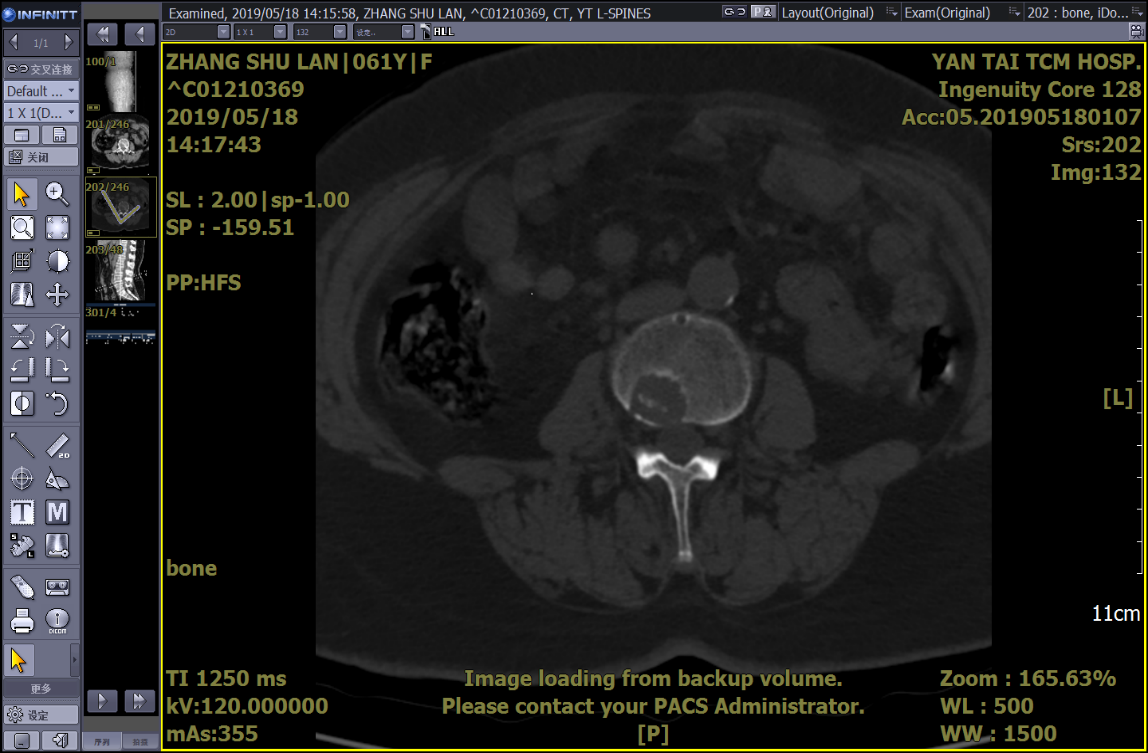

PET-CT示:1.腰3椎體(tǐ)局限性骨質破壞,FDG代謝輕度增高;股骨頸局限性骨質破壞,周圍軟組織受侵、腫脹,局部條狀骨骼密度影(yǐng),FDG代謝增高。右側顱骨及腰椎多個椎體(tǐ)骨質破壞、胸椎多個椎體(tǐ)低密度影(yǐng),FDG代謝不高。考慮骨髓瘤?

床頭攝片:右股骨小轉子遊離(lí),請(qǐng)結合臨床。

骨穿,行骨髓免疫分(fēn)型示:共檢測有核細胞260000個,異常漿細胞占有核細胞6.8%,表達cKappa,CD138,CD38,CD81,CD56,CD28。部分(fēn)表達CD200,不表達cLambda,CD27,CD117,CD19,CD20。結合血鈣升高、單克隆免疫球蛋白(bái)升高等,确定診斷:多發性骨髓瘤。

因患者存在椎體(tǐ)及股骨頸骨損,患者目前隻能扶杖行走,爲了能夠更好地改善患者生(shēng)活質量,預防病理性骨折發生(shēng),需要對如(rú)下骨損進行外科幹預治療。